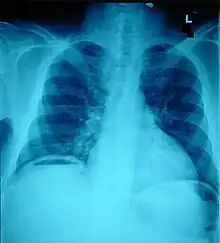

Pneumoperitoneum, seen as an air bubble on the lower left side of the X-ray film